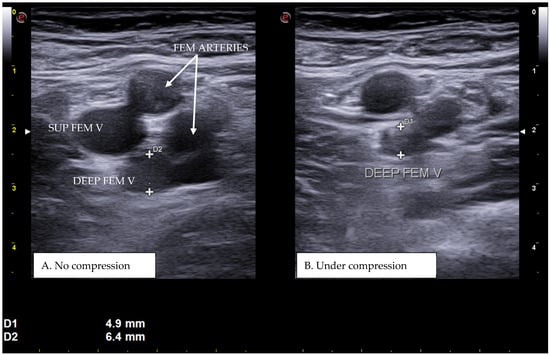

Figure 1. A real example of deep femoral vein thrombosis at the level of the upper left thigh (groin region). D1 shows the residual diameter of the non-compressible vein (i.e., the maximum diameter of the relative venous thrombus). D2 represents the venous diameter without compression.

CUS is a diagnostic technique primarily designed to find DVT by checking the veins’ compressibility with the principle that healthy veins are normally compressible and would collapse under the pressure of the ultrasonographic probe. In the case of the presence of a venous thrombus, the vessel would not be able to collapse under such pressure [8,9]. Linear high-frequency transducers are generally used for CUS as they best visualize leg veins [10]. The ultrasound machine settings must be adjusted carefully in order to limit possible operator-related bias. Important elements to be considered in this setting include gain, focus, and time-gain compensation. Gain adjustment regulates image brightness, focus optimization sharpens the image to the desired depth, and time-gain compensation enhances the visibility of subtle echoes, ensuring uniform image quality [10,11]. The transducer partially compresses the vein, which creates an echogenic response. In normal veins, this technique should fully compress the lumen [9]. However, with thrombosis present, the vein does not collapse enough, which causes a non-continuous echogenic line [12]. While the femoral veins are usually well identified in the groin and thigh areas, to facilitate better visibility of the popliteal veins, the patient may lie in a supine position with the leg slightly abducted to relax the muscles or, alternatively, in a prone position [9]. Real-time B-mode and Doppler imaging are both valuable tools in this process. B-mode imaging can find incomplete vein collapse during compression [13,14]. Doppler imaging can show the thrombus or find a complete lack of flow in the lumen [9]. As such, CUS for DVT diagnosis involves evaluating direct signs like the presence of a non-compressible echogenic line suggesting a thrombus, as well as indirect signs like changes in vein compressibility and thrombus echogenicity [6,7]. In addition, evaluation of flow patterns and flow response during augmentation maneuvers may refine the diagnostic examination, although their implementation requires more advanced training and skills than simple CUS [7]. Clinicians should assess a spectrum of veins, including the external iliac, common femoral, superficial and deep femoral, popliteal, tibial, peroneal, gastrocnemial, and soleal veins, as well as the junctions with the great and small saphenous veins, representing the superficial systems [15]. Challenges exist in visualizing the iliac veins, especially in obese patients, yet phasic flow in the femoral veins can be indicative of DVT status, particularly for excluding iliac vein thromboses [16]. This comprehensive approach is standard in differentiating healthy veins, which should collapse and enlarge with augmentation maneuvers, from those with thrombosis, which show impaired response to pressure and flow changes [12,17]. Figure 1, Figure 2, Figure 3 and Figure 4 show real examples of DVT affecting different sites of the lower limb deep venous system, diagnosed through a CUS modality.